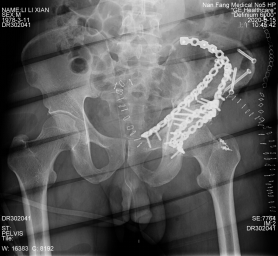

擅长复杂骨盆、髋臼骨折大出血急救,肢体离断伤与严重开放性骨折急救、显微外科断指(趾)再植、保髋手术治疗、创面修复、骨折内固定及骨搬运修复重建手术。在骨盆、髋臼骨折,老年骨折,关节周围等复杂骨折手术,在显微外科、足踝外科、骨肿瘤、骨感染、骨不连、糖尿病足、儿童骨折等疾病领域特色明显。